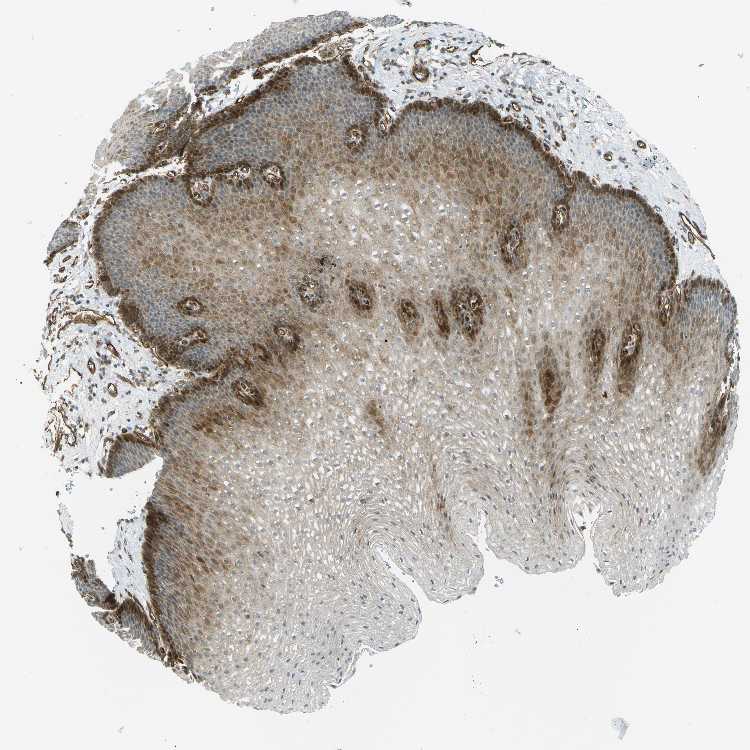

ESOPHAGUS - Antibody stainingi

Antibody staining in the annotated cell types in the current human tissue is reported as not detected, low, medium, or high, based on conventional immunohistochemistry profiling in selected tissues. This score is based on the combination of the staining intensity and fraction of stained cells.

Each image is clickable and will lead to virtual microscopy that enables deeper exploration of all samples and also displays staining intensity scores, fraction scores and subcellular localization as well as patient and tissue information for each sample.

Antibody CAB010104

Squamous epithelial cells Medium